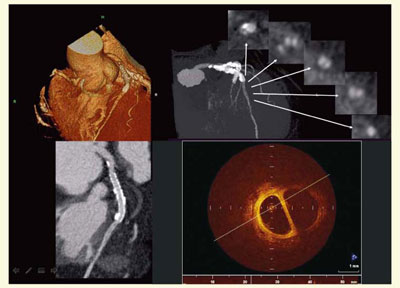

● 症例5:IRISによる石灰化除去

逐次近似法を用いた画像再構成法であるIRISによるノイズ低減と,DEイメージングを用いた石灰化除去を試みた(図8)。トライアル段階だが,従来のバックプロジェクション(FBP)法に比べて,血管壁がスムーズに描出されている。

図8 症例5:IRISによるノイズ低減と石灰化除去の試み

● 症例6:冠動脈治療効果判定

Definition Flashによる心臓CTで期待されるのは,冠動脈疾患に対する治療効果の評価である。プラークの脆弱性をCTで判定し,治療効果の指標に使うことができれば,薬物療法の治療効果をCTでモニタして,外来での管理が可能になる。最初の段階として,PCIの際にDefinition Flashの画像とIVUSなど他のモダリティとの比較検討を行い,CT画像の有用性を検証している。図9は,留置されたステントの先に新たな狭窄(→)が認められた症例で,ステント内再狭窄は認められなかった。ストロングスタチンで治療を行ったにもかかわらず,病変が進行した。狭窄度は75%程度だったがCT値が低く,PCIが施行された。

図9 症例6:冠動脈治療効果判定